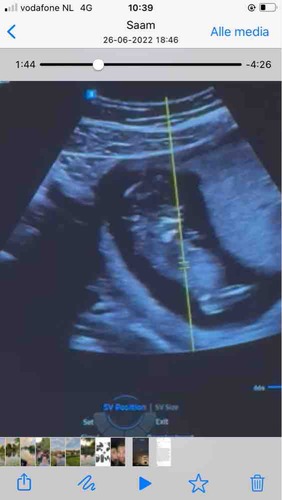

Blauw: omranding

Rood: Blaas

Groen: stand nub en blaas met ruggengraad

Zoals je kan zien in de ingezoomde echos met alleen blauw zie je een klein bolletje/boven de nub lijn. Dit is normaal het begin van de ontwikkeling van de pipi

De lijn van de nub veranderd dan in de balletjes.

Zoals op de echo met de andere kleuren lijnen is er meer schaduw bij gedaan waardoor je ook duidelijker ziet dat de nub omhoog staat. De blaas zit ook erg laag en van nub naar blaas naar ruggengraad staat het in een hoek naar de ruggengraad(📐) dit duidt op een jongen. Bij meisjes loopt het gelijk of bijna gelijk aan de ruggengraad(=) de blaas zit daar dichter tegen de nub aan en is de nub plat en is er geen bolletje.